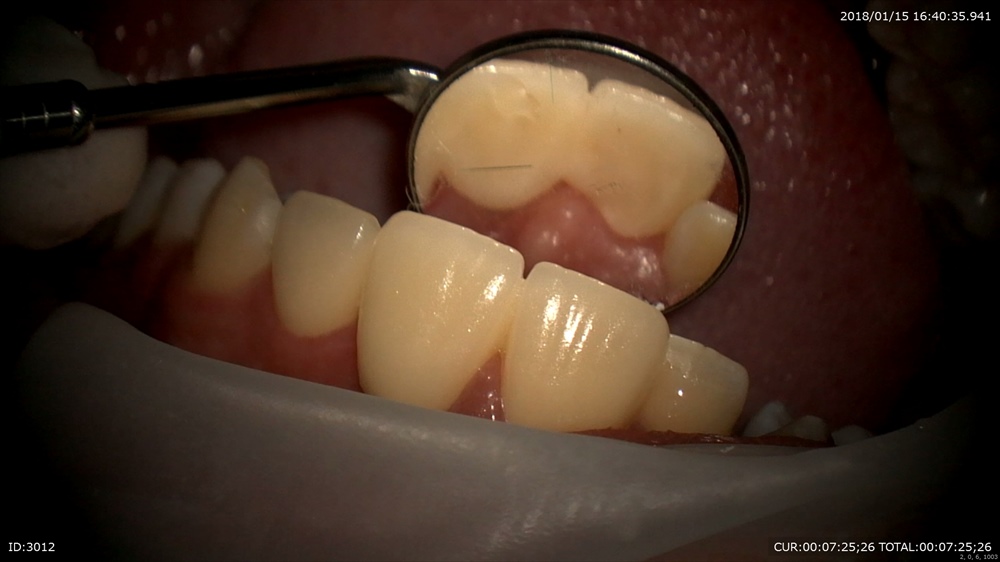

1ケース目

「ブリッジを前回いれて少ししみる。噛むと少し痛い。」

不安になっていました。

不安を解消するために、生きている歯を一周削るブリッジの治療の弱点をマイクロスコープの実際のこの患者さまの施術シーンを振り返りました。すべて録画し日にち別で保管しているからすぐ出来る設備です。

今日

フィットは問題なし

ここから今回のこの画像(動画)と今までの治療を時系列で比較します。

こんなに削るのですね。と関心されていました。見ないと解りませんものね。

このようにすべて動画でお見せし、痛みの可能性やこれからの注意事項をお話できます。当院に来院している皆様に行っていますので通院中の方は良く見る画像ですよね。安心してお帰りになりました。ホッとしました。